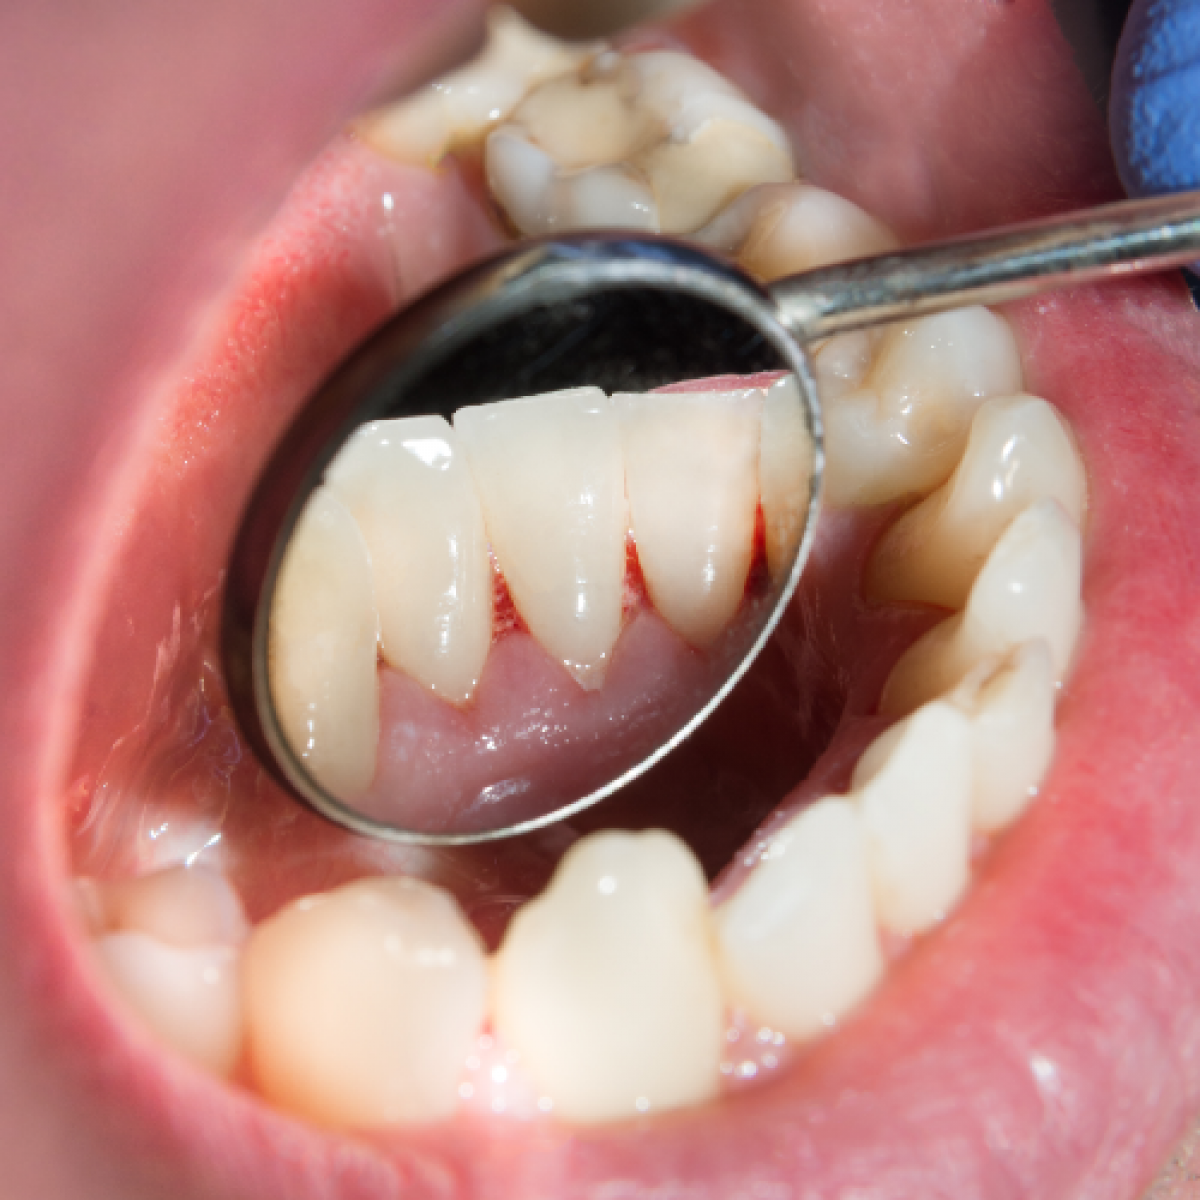

Periodontal evaluations were assessed to patients at the Dental Clinic of Padua for the preventive odontostomatological visit to zoledronic acid therapy (Zometa®) (Casi Group). The first group was then compared with a second group comparable in age, gender, diabetes, smoking and systemic diseases not related to the pathology for which therapy with zoledronic acid (Zometa®) (Control Group) was indicated. The computerized periodontal file of the University of Bern was used to record the periodontal parameters. Each patient, during the visit in the presence of imaging, through the use of a Williams and Nabers periodontal probe, was assigned a periodontal status assessment referring to the new 2017 classification of periodontal and peri-implant diseases during the visit.

In the Casi Group an average BoP (%) equal to 25.26 and an average percentage presence of plaque (%) equal to 35.53 was detected while in the Controls group an average BoP (%) was detected 35.73 and a percentage presence of plaque (% ) average equal to 25.46. The difference in BoP (%) and Plaque percentage presence (%) is statistically significant. The results of the application of the new classification of periodontal and peri-implant disease showed that, in the Cases group, 6.67% of patients had a state of health, 16.67% was associated with stage 1, 3.3% is been associated with stage 2, 40% were associated with stage 3 and 33.33% with stage 4. Grade A was associated with 57.14% of patients in the Cases group, Grade B with 35.71% and 7.14% grade C. The extension of periodontal disease in the Cases group was generalized in 47.37% of patients and localized in the remaining 55.56%. The results of the application of the new classification of periodontal and peri-implant disease showed that 6.67% of patients in the Controls group were in a state of health, 3.33% were associated with stage 1, 16.67% were associated with stage 2, 43.33% was associated with stage 3 and 30.00% with stage 4. Grade A was associated with 35.71% of the Control group patients, grade B with 60.71% and 3.57% grade C. The extent of periodontal disease in the Controls group was generalized in 52.63% of patients and localized in the remaining 44.44%. The comparison between the results derived from the application of the new periodontal classification carried out through the Fisher's Test, showed that there is no statistically significant difference between the two groups (p> 0.05). This result shows how the periodontal status of patients with indications for zoledronic acid therapy for oncological diseases reflects that of the general population.

The new periodontal classification classify patients based on risk factors and periodontal status and the risk of progression of periodontal disease, this allows to obtain a univocal evaluation that facilitates the sharing of data between clinicians and allows a good management over time of patients.